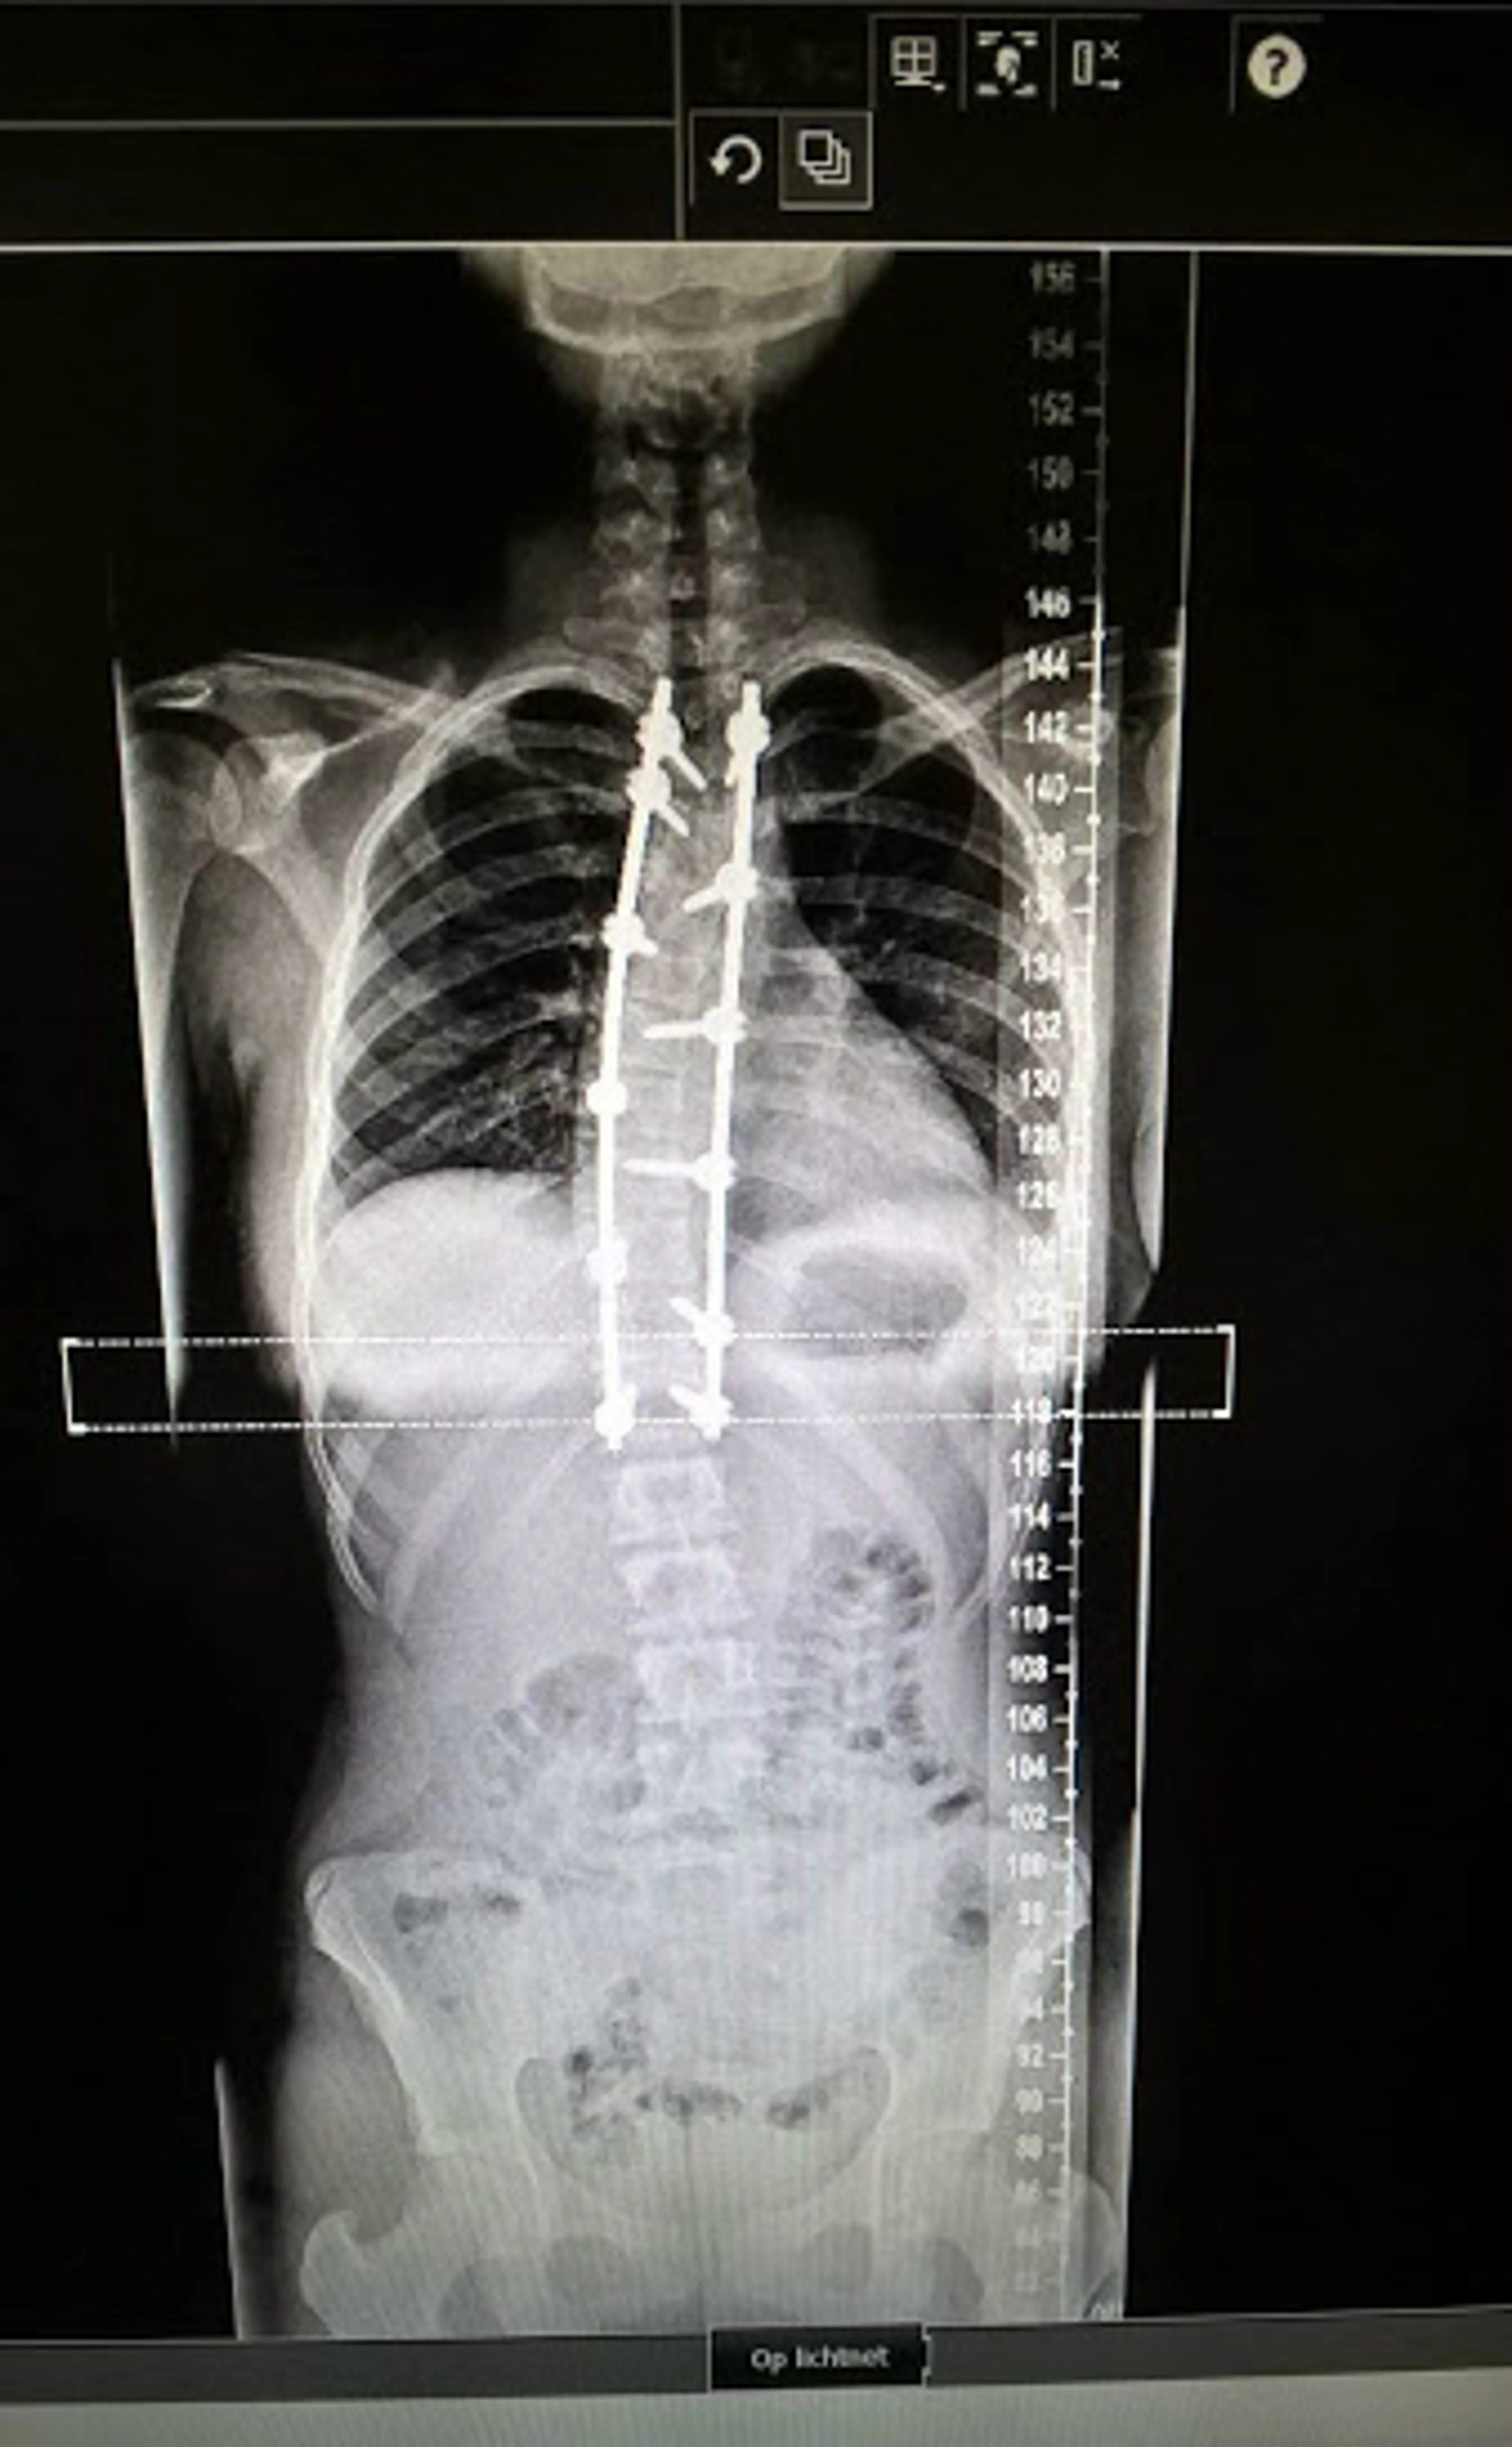

Bij de dokter moest ik een buktest doen. Er wordt dan gekeken of er ongelijkheden zijn in de stand van je ribbenkast. Bij mij stond de rechterhelft veel hoger, omdat mijn ribbenkast gedraaid stond, vanwege de bocht in mijn wervelkolom. Het was voor de huisarts direct duidelijk dat ik een scoliose had. Ik had geen idee wat een scoliose was, dus dat heeft ze allemaal uitgelegd. De huisarts stuurde mij toen door naar de orthopeed. Daar heb ik een röntgenfoto laten maken. De orthopeed mat een bocht van veertig graden. Mijn scoliose is ontstaan tijdens de groeispurt in de puberteit."

"De maanden, weken en zelfs dagen voor mijn operatie was ik dan ook helemaal niet zenuwachtig. Ik had er zelfs zin in! Ik vertrouwde volledig op God. De operatie verliep goed en ze hebben de bocht kunnen rechttrekken tot dertien graden. Rechter trekken dan dat was te risicovol, vanwege alle zenuwen in je ruggengraat en de kans op een dwarslaesie.